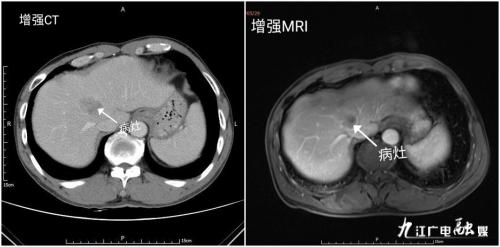

近日,生命活水医疗集团总院肝胆胰外科收治一例外院诊断考虑胃癌合并肝转移癌的中老年男性患者。因患者病情复杂,生命活水医疗集团总院肝胆胰外科立即开展多学科协助诊疗模式(MDT),邀请院内的普外科、消化内科、病理科及肿瘤科综合讨论。同时结合腹部增强CT、腹部增强MRI、AFP及胃镜活检病理,肝占位考虑原发性肝癌,并非转移癌。诊断考虑患者为同时性肝癌合并胃癌多原发性癌,且有手术指证,一致建议限期行肝癌及胃癌根治性手术治疗。

多原发癌指同一病人同时或先后患2种或2种以上的原发性恶性肿瘤,其中每一肿瘤均为恶性。每一肿瘤在组织病理学上相互独立且除外复发或转移情况,是一种较罕见疾病。两个癌灶发生时间间隔在6个月以内称为同时性多原发癌,6个月以上为异时性多原发癌。肝癌是我国常见的恶性肿瘤,目前,国内外有关合并肝癌多原发癌研究较少,胃癌合并肝癌多原发癌的病例报道少之甚少,多原发癌与胃癌肝转移的预后截然不同,治疗方案亦有所区别。而且,该患者胃癌诊断明确,术前超声、CT、MRI检查发现肝占位,须鉴别是原发性肝癌还是胃癌肝转移。结合影像学及AFP升高,所以高度怀疑患者为胃癌合并原发性肝癌。故在诊治过程中,应考虑到两种肿瘤并存的可能。